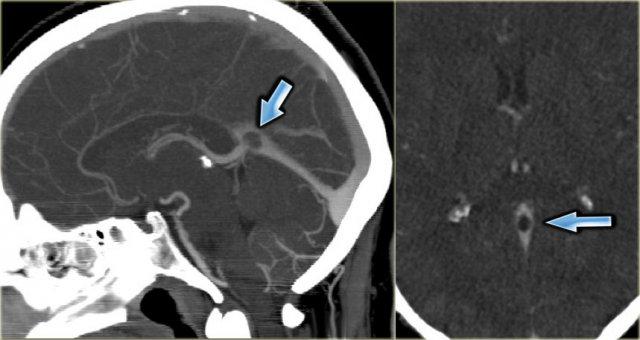

Huyết khối và tăng áp lực dịch não tủy

Ở một số bệnh nhân, huyết khối xoang màng cứng có thể dẫn đến rối loạn tuần hoàn tĩnh mạch kéo dài, ngay cả sau khi đã tái thông.

Tình trạng này có thể gây tăng áp lực dịch não tủy nội sọ, được đánh giá qua chọc dò thắt lưng.

Về lâm sàng, các bệnh nhân này thường than phiền đau đầu và có thể có rối loạn thị giác do phù gai thị.

Trên MRI, có thể thấy tăng lượng dịch não tủy quanh dây thần kinh thị giác và hình ảnh hố yên rỗng.

Có vẻ như ở một số bệnh nhân vẫn tồn tại hẹp tồn dư.

Hình ảnh chuỗi xung T2W bên trái cho thấy phù gai thị và hình ảnh hố yên rỗng.

Tiếp tục xem hình ảnh chuỗi xung T1W mặt phẳng đứng dọc.

Đây là hình ảnh chuỗi xung T1W mặt phẳng đứng dọc cho thấy hình ảnh hố yên rỗng (mũi tên).

Thuật ngữ “hố yên rỗng” được dùng vì hố yên chủ yếu được lấp đầy bởi dịch não tủy do tuyến yên bị đẩy xuống dưới bởi áp lực nội sọ tăng cao.